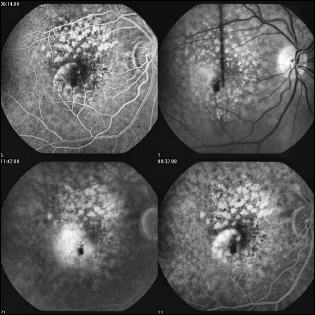

Fluoreszenzangiogramm: die krankhafte weiße Gefäss-Veränderung ist auf dem Bild oben nicht sichtbar

Was ist eine Fluoreszenzangiographie (FLA)? Die Fluoreszein-Angiographie (“Gefäßdarstellung”) dient dazu, Veränderungen am Augenhintergrund und dort insbesondere an den Blutgefäßen festzustellen. Viele dieser Veränderungen sind auch unter dem Mikroskop nicht ausreichend gut zusehen, so dass erst die Angiographie-Bilder Sicherheit in der Diagnosestellung und Therapie geben. (Wie beim Eisberg verbirgt sich häufig der größte Brocken unsichtbar in der Tiefe)

Was passiert bei der Untersuchung? Diese Untersuchung ist bis auf die Anwendung einer Venenverweilkanüle (wie beim Blutabnehmen) völlig schmerzfrei und besteht im Wesentlichen aus einer besonderen Form einer Augenhintergrundsfotografie. Für ein gutes Ergebnis der Untersuchung wird eine sehr gute Pupillenerweiterung benötigt – das kann häufig längere Zeit beanspruchen als für eine schon gewohnte Augenhintergrund - Untersuchung bei Ihrem Augenarzt. Bitte richten Sie sich, aufgrund der aufwändigen Untersuchung, auf eine Aufenthaltsdauer in unserer Praxis von ca. 2 Stunden ein. Ihnen wird während der Untersuchung ein wässriges Fluoreszenzmittel in die Armvene gespritzt, das mit einer Spezialkamera Undichtigkeiten im Blutgefäßsystem aufdeckt. Vergleichen Sie es mit einem Fahrradfahrer der einen „Platten“ hat und das unsichtbare Loch in seinem Schlauch finden will: ohne die Zuhilfenahme eines Eimer Wasser, in den er den Schlauch hält, sieht er die Luft nicht entweichen, die ihm das Leck zeigt.